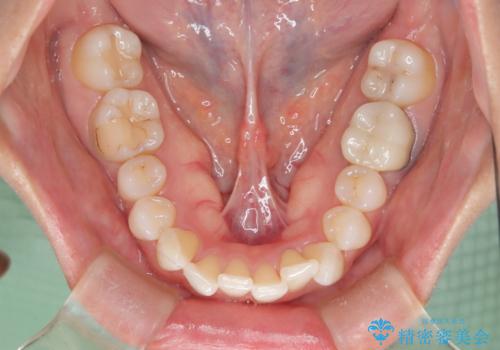

- 前歯のガタつき、変色を主訴に来院された患者様です。術前診査のCT撮影にて、変色した前歯の根の先に病巣があることが判明しました。そこで、マウスピースによる矯正治療と、前歯の根管治療、かぶせ物のやり直し治療を並行して行いました。